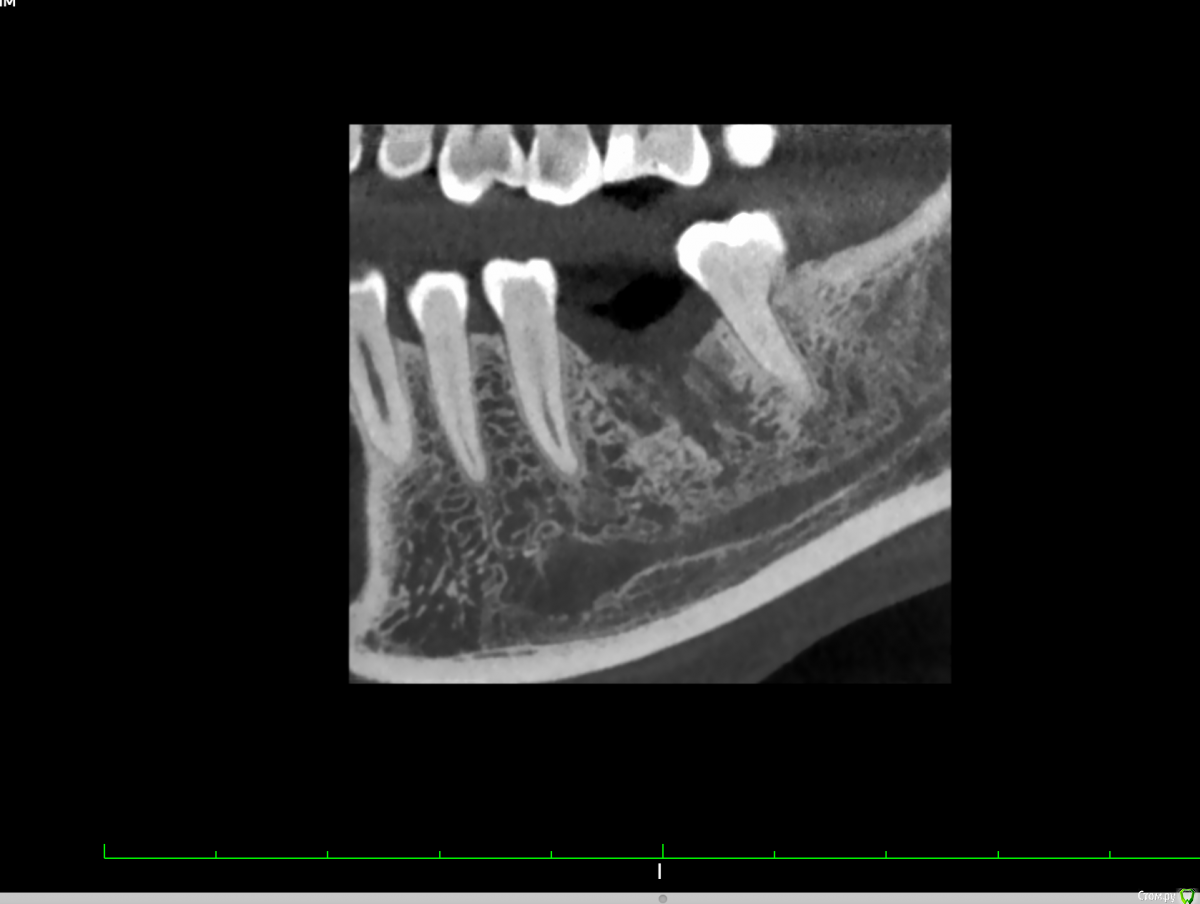

Valerkaa Опубликовано 13 сентября, 2019 Поделиться Опубликовано 13 сентября, 2019 Добрый день, коллеги. Помогите, пожалуйста, советом. Планируется имплантация, удаление было в феврале. Смущает состояние кости. Понятно, что можно раскрыться, и если грануляции, то кюретаж. Просто морально хочется понимать, чего ждать. Была ситуация, когда с похожей картиной на КТ раскрылась, кость была визуально норм, но через месяц имплант просто пинцетом достала.Собственно вопрос: нормальное ли это состояние кости через полгода после удаления или все-таки что-то не так и надо морально готовиться к кюретажу? Опыт в имплантации совсем небольшой, поэтому такие вопросы возникают)) Ссылка на комментарий

Евгений Ходыкин Опубликовано 13 сентября, 2019 Поделиться Опубликовано 13 сентября, 2019 Будет кюретаж, всё верно. 2 Ссылка на комментарий

dr Alexandr Опубликовано 14 сентября, 2019 Поделиться Опубликовано 14 сентября, 2019 Нужен кюретаж, что б потом не готовиться морально к удалению имплантанта!..подготовить кость и спланировать операцию, возможно понадобиться подсадка кости. Ссылка на комментарий